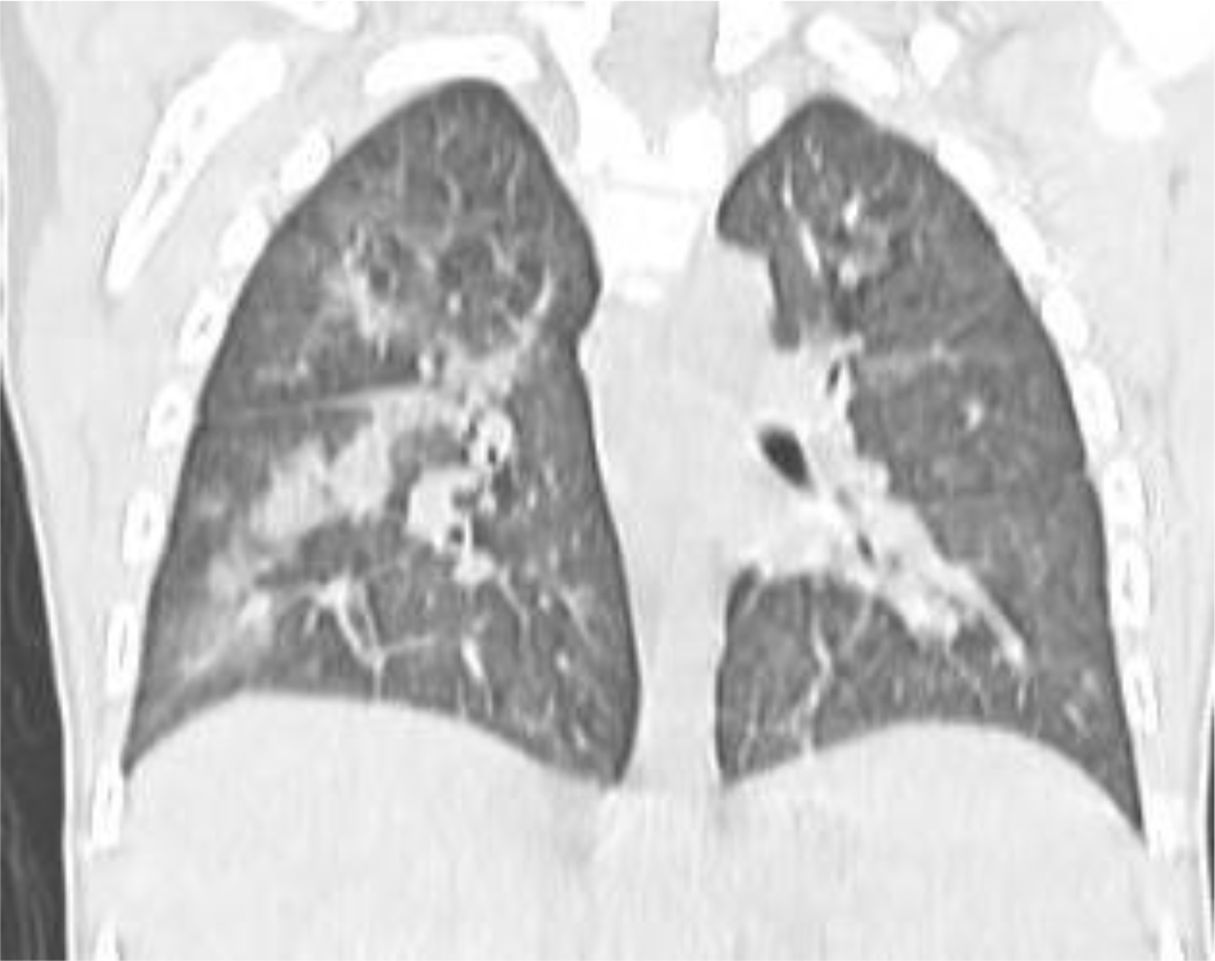

A 4 year-old male was diagnosed with HbE/Beta-thalassemia at age 2 years, and had received monthly red blood cell transfusions since. He was found to have a fully matched sibling and was scheduled for HSCT. At pre-transplant evaluation he was found to have mild hemophilia A, with no history of bleeding, and borderline low factor VIII levels discovered because of prolonged PTT at routine pre-anesthesia workup. His baseline FVIII was in the 10-20% range. He had received FVIII supplementation with PTT normalization and 28% FVIII levels. HSCT preparation consisted of fludarabine total dose 200 mg/m2, and dexamethasone total dose 125 mg/m2 on days -40 to -36, fludarabine total dose 180 mg/m2 on days -11 to -6, busulfan oral total dose 14 mg/kg from day -9 to -6, cyclophosphamide total dose 200 mg/kg from day -5 to -2. The graft source was G-CSF-primed marrow, and rejection/graft vs. host disease prophylaxis consisted of cyclosporin A and short course methotrexate. Neutrophil engraftment occurred on day +19. On day 21st post-BMT, while platelets were 18.000/µL and had received the last platelet transfusion 3 days before, he developed dry cough, respiratory distress, and hypoxemia, followed one day later by hemoptysis. He underwent a lung CT scan and found to have interstitial lung disease with areas of ground glass bilaterally, mainly in the lower lobes (Figures 1, 2). FVIII was 28%. He was diagnosed with DAH and was treated with additional FVIII concentrate (Advate), blow-by oxygen supplementation, red blood cells transfusion, platelet transfusion, methylprednisolone, tranexamic acid, and antioxidants (vitamin C and E). A chest CT repeated the following day should no hemorrhage progression and partial reabsorption of the bleeding (Figure 3). Methylprednisolone therapy was discontinued. The child had a complete clinical and radiological resolution in 6 days. (Figure 4). He had good engraftment and otherwise uneventful post-transplant course with a 4-month follow-up at the time of this report (Table 1).

CT scan of the chest showing a large, round mass in the right lung. Surrounding lung tissue is visible with branching vascular patterns. The mass appears more radiopaque compared to lung tissue.

Figure 4. CT scan six day after diagnosis.